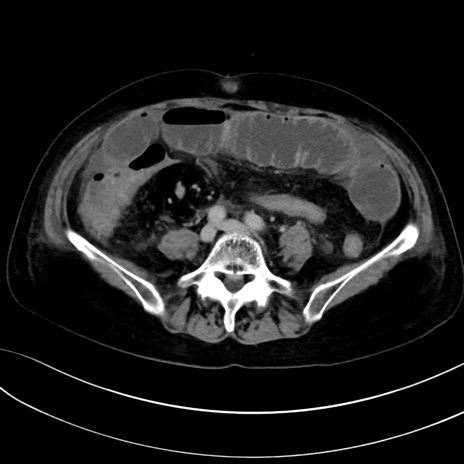

(冠状断像)1日半後